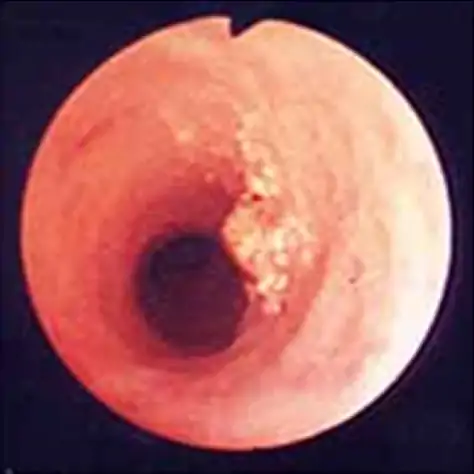

胆道内視鏡